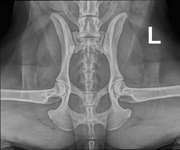

Unsere Hündin, die wir jetzt 4 Monate haben, musste zur Blutabnahme. Verdacht auf Leishmaniose. Sie kommt aus Kroatien und es geht ihr seit einer Woche nicht gut.